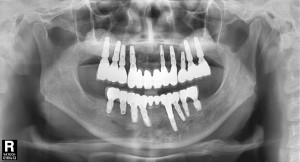

치료 중 찍은 방사선 사진입니다.

치료 필요에 따라 뼈이식도 진행하였습니다.